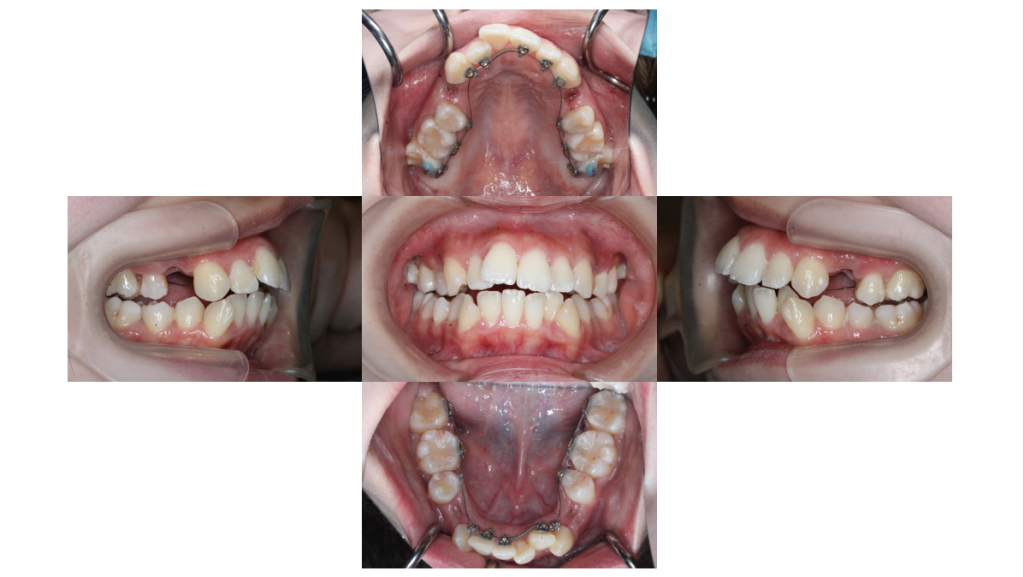

上下装置装着

叢生・裏側矯正の症例上下装置装着直後の口腔内です。